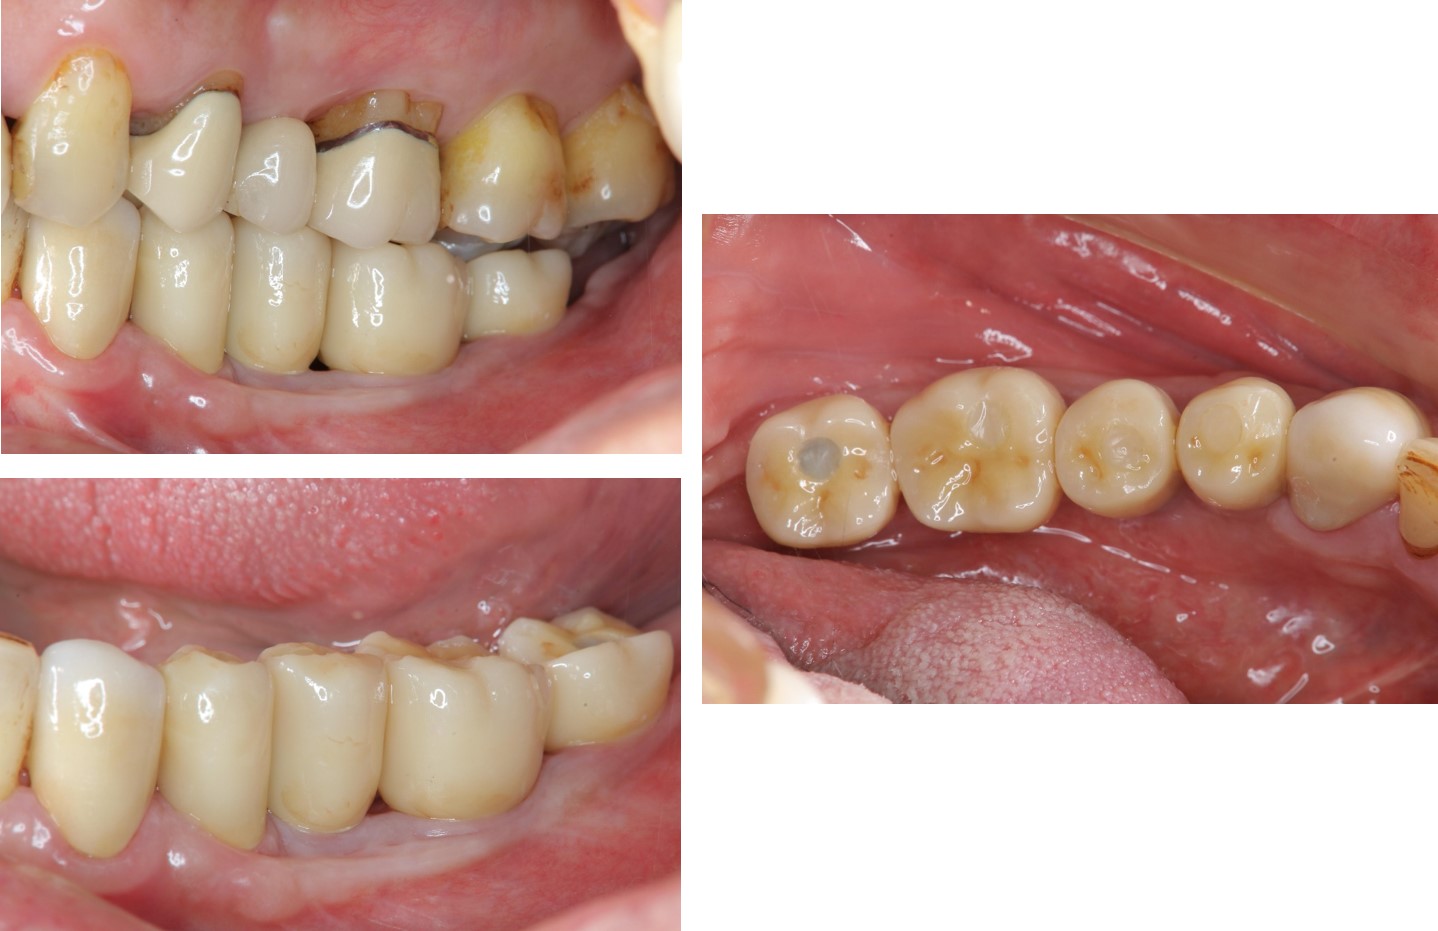

▼自然牙與植牙單顆全瓷冠(第一次看到植牙本人,超神奇!!!)

治療後,口內照(終於!我家人的牙齒回來了,雖然看不太習慣,但我家人說她終於找回當年有牙齒的感覺了~果然缺牙還是口腔有問題,找醫生就對了,一般人哪可能自己生出牙齒來!)

自然牙與植牙單顆全瓷冠:#33-37

治療後,口內照